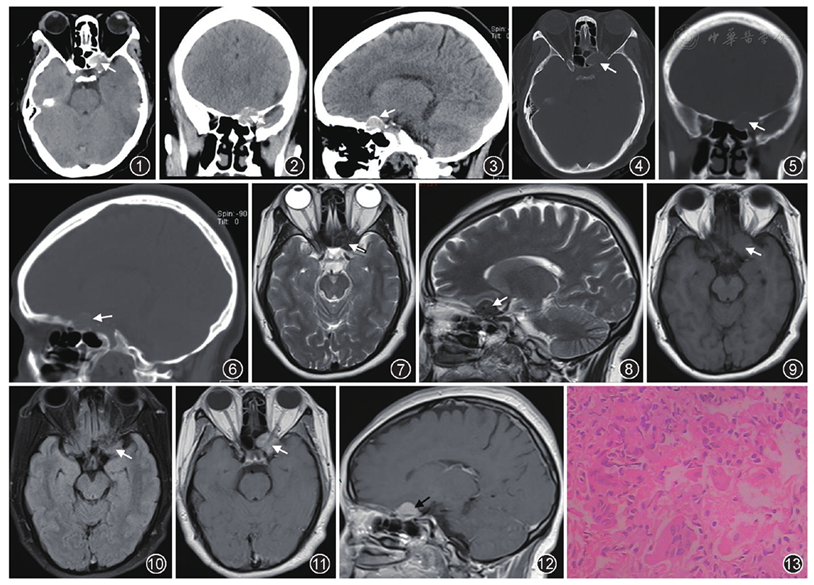

蝶骨骨母细胞瘤一例误诊分析 - 中华放射学杂志